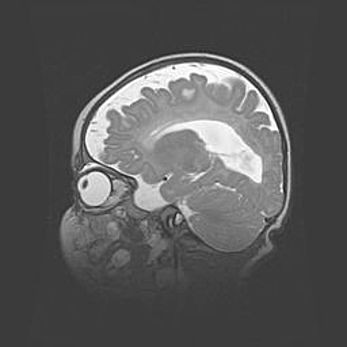

Мальформация Денди-Уокера. Киста задней черепной ямки.

Агенезия мозолистого тела.

Возраст: 2,5 месяца

Вес: 2420 г

Пол: женский

Окружность головы: 37 см

Срок гестации: 32 недели

Мальформация Денди—Уокера — редкий вид патологии ЦНС, представляющий собой врожденный порок развития каудального отдела ствола и червя мозжечка, ведущий к неполному раскрытию срединной (Мажанди) и латеральных (Лушка) апертур IV желудочка мозга. Для этогно синдрома характерна триада симптомов: гипотрофия червя мозжечка и/или полушарий мозжечка, кисты задней черепной ямки, гидроцефалия различной степени. В 70% случаев порок сочетается и с другими аномалиями головного мозга, в частности с агенезией мозолистого тела.